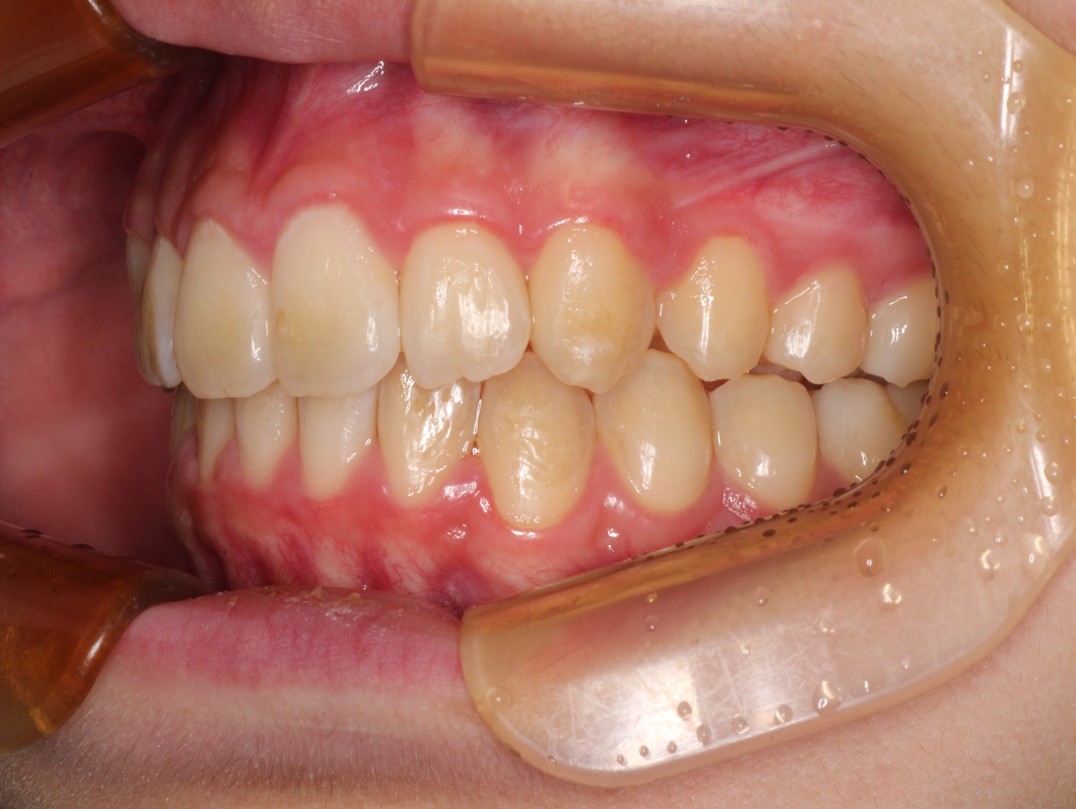

治療後

Ⅰ期治療は前歯の歯並びだけを揃えましたが、奥歯の歯並びも綺麗にしたいとのことだったのでⅡ期治療も行いました。 |